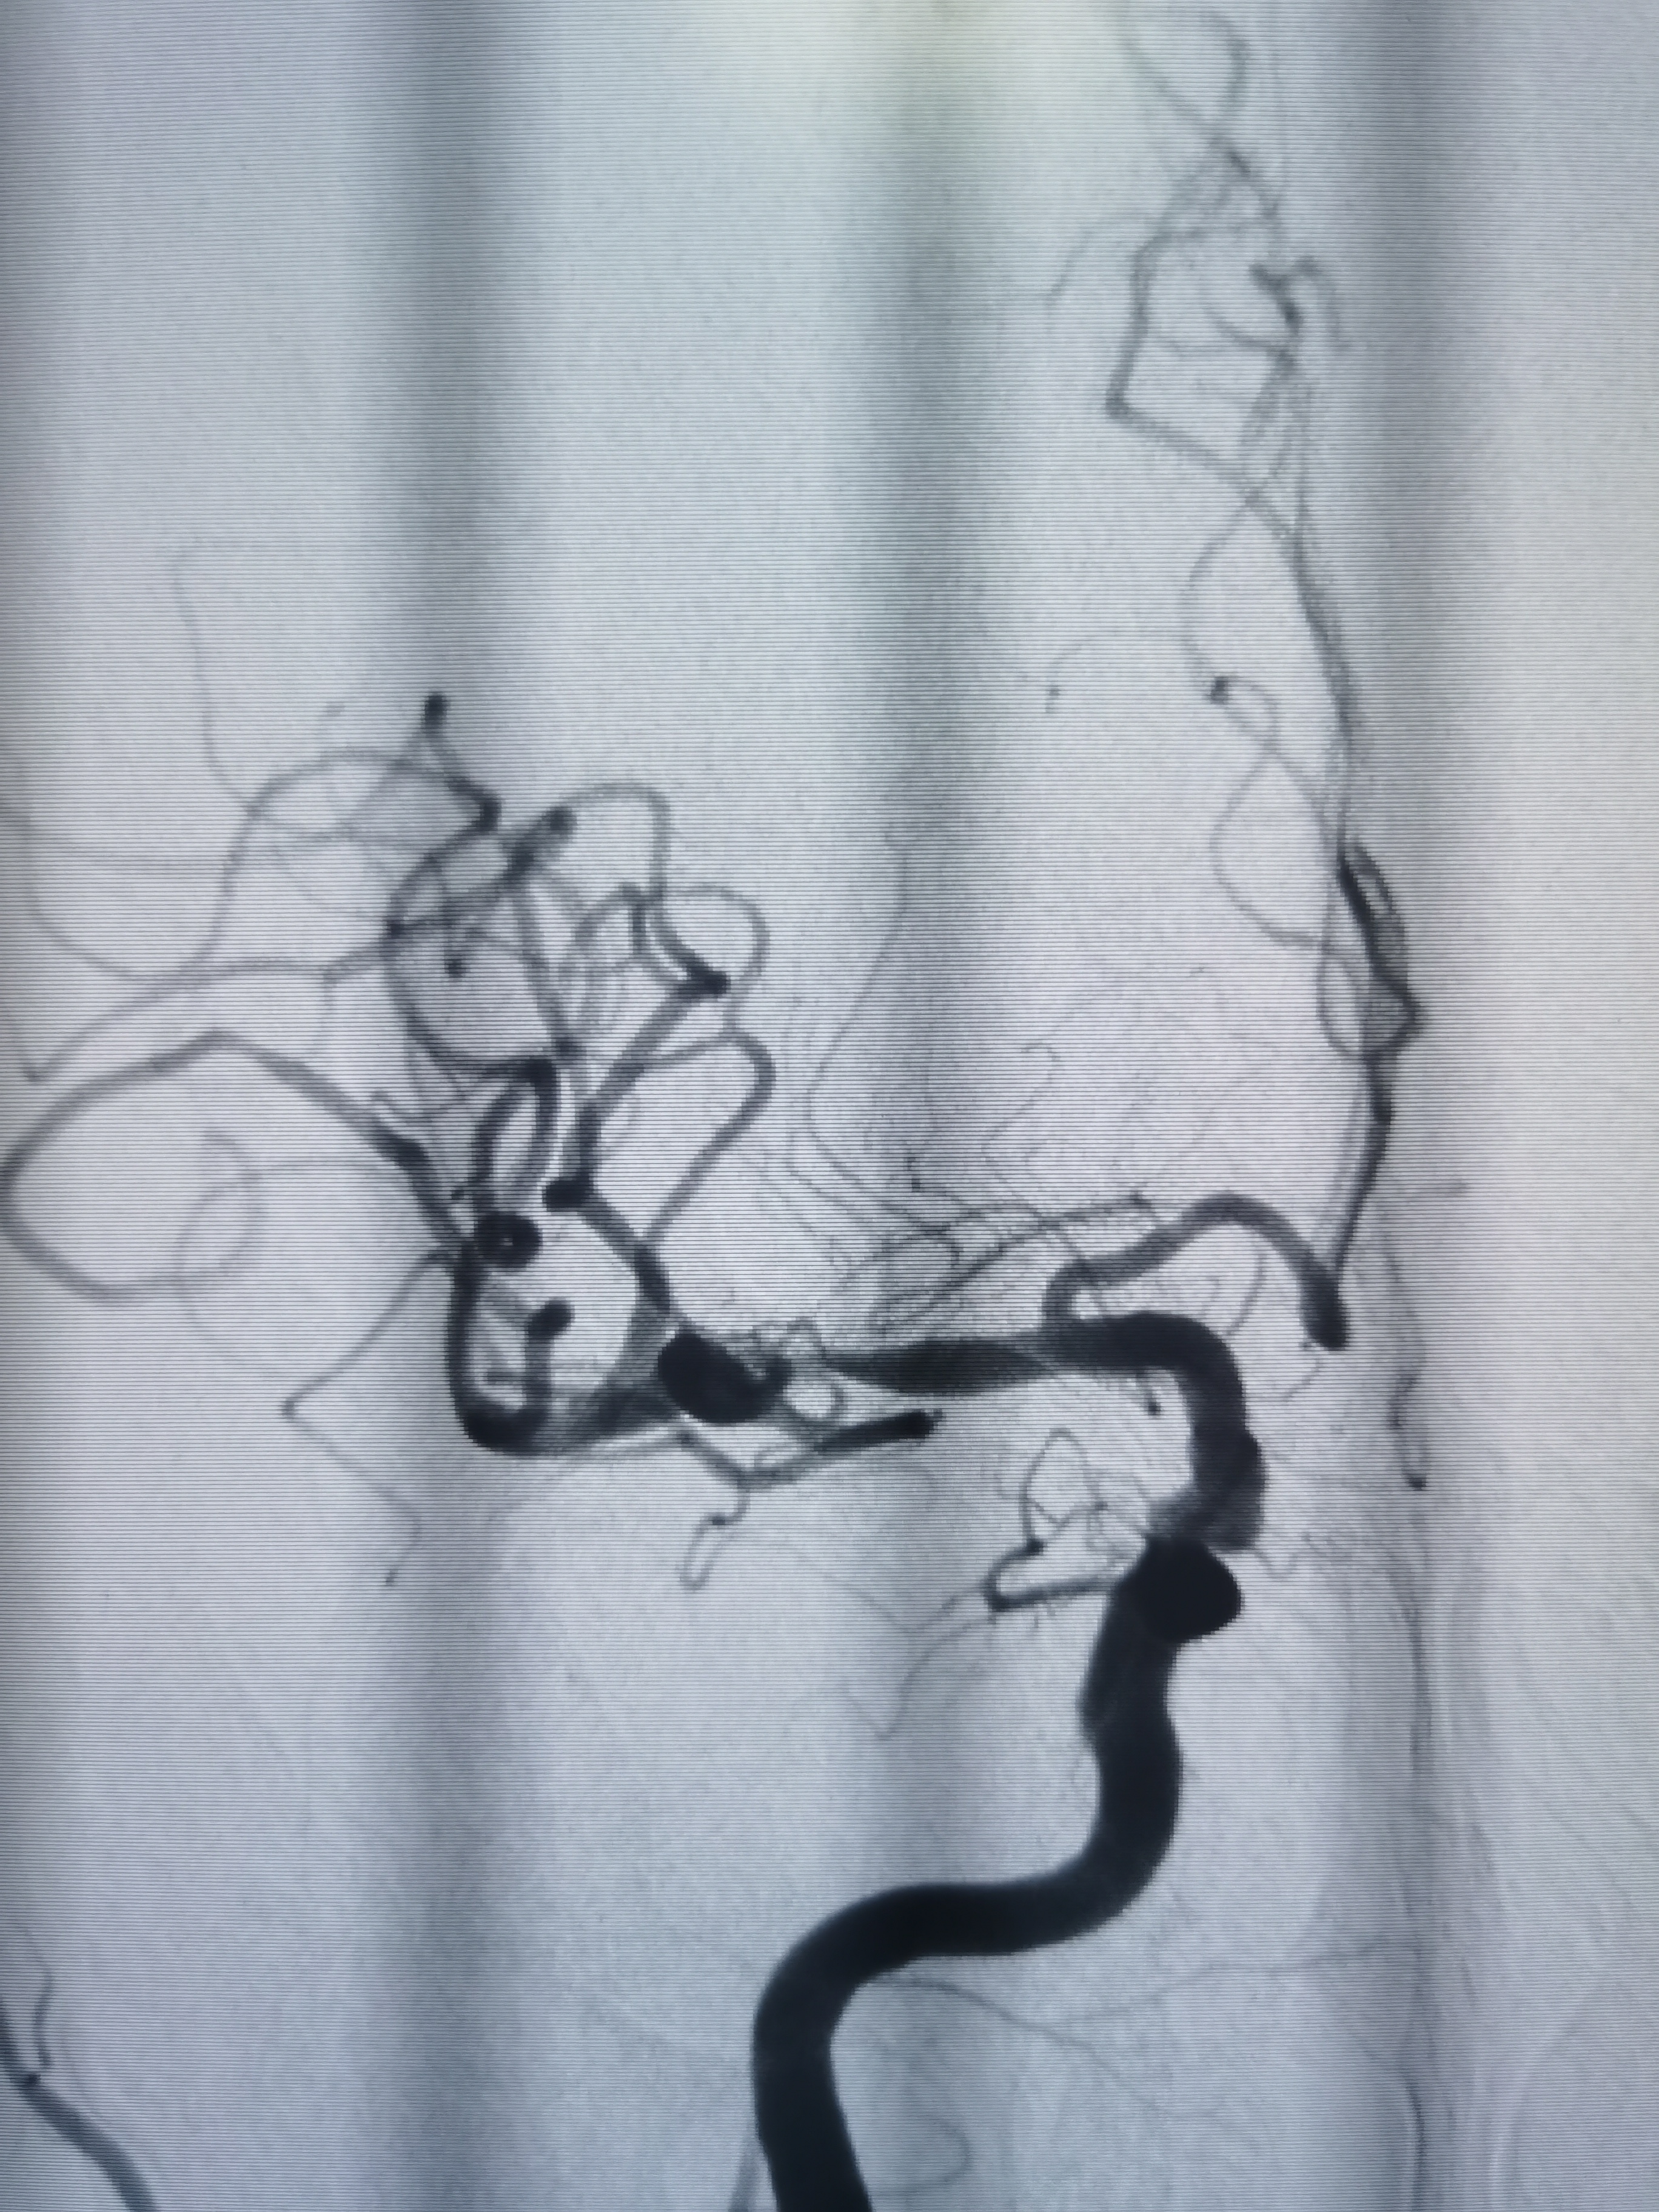

术后即刻造影见动脉瘤栓塞较完全。

术后造影见动脉瘤栓塞较为完全,载瘤动脉通畅,遂未再植入支架,逐渐撤出各级导管,缝合股动脉结束手术。